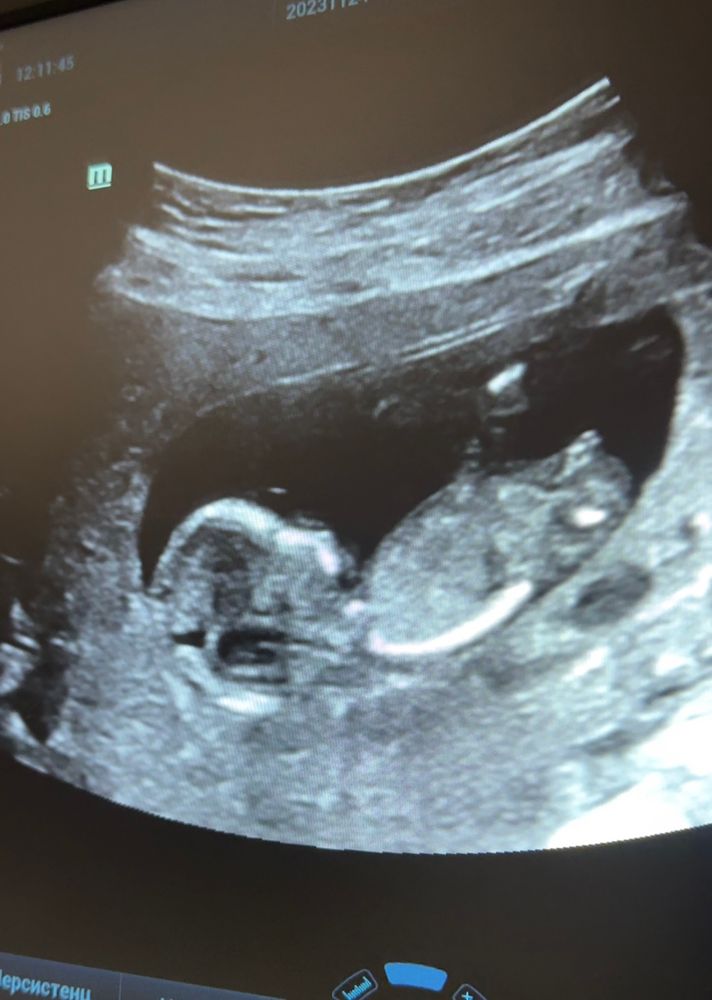

Айка в Благополучная беременность 2 года Мальчик или девочка? УЗИ, КТГ, доплер Кто нибудь разбирается в углах наклона? Как думаете, кто у нас тут?🤔 Посмотрите еще 20 записей на эту тему Отменить Ответить ♥ Ангелочек ♥ Девочка 27.11.2023 Ответить Юля Девочка. 26.11.2023 Ответить Не обязательно На первом фото мальчик, на втором девочка 🤭😅 26.11.2023 Ответить Мария А как вы это понимает? 26.11.2023 Ответить elena Девочка 26.11.2023 Ответить Виктория Девочка 26.11.2023 Ответить Svetlana Девочка похожа 26.11.2023 Ответить Док Валерия Мой хрустальный шар говорит что это девочка 26.11.2023 Ответить 31 ДПП 🤍 УЗИ Два желтых тела и одно плодное яйцо Чаты Беременных Выберите чат: Январята-2026 Февралята-2026 Мартята-2026 Апрелята-2026 Майчата-2026 Июнята-2026 Июлята-2026 Августята-2026